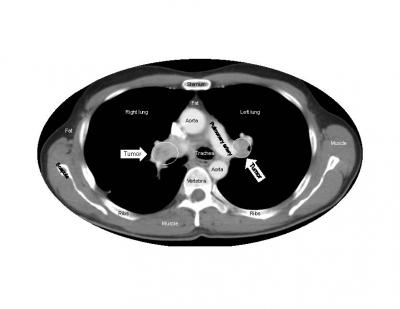

Studies in animals have raised concerns that tumors may grow faster after the anticancer drug sunitinib is discontinued. But oncologists and physicists who collaborated to analyze data from the largest study of patients with kidney cancer convincingly demonstrate that such tumor acceleration does not occur in humans. The findings, publishing online on February 7th in the Cell Press journal Cell Reports , suggest that sunitinib does not cause lingering risks for patients after their treatment ends.

Sunitinib, which is approved around the world for the treatment of several different cancers, works by targeting proteins on the blood vessels that feed tumors. Animal studies have suggested that treatment with sunitinib may induce changes in tumor vessels or adaptations within tumors themselves that could promote cancer growth and spread.

When Dr. Fojo and his colleagues analyzed more than 10,000 data points from the pivotal randomized phase 3 clinical trial that led to sunitinib's approval, the evidence clearly showed that no matter how long patients took sunitinib, it was not harmful, did not accelerate tumor growth, and did not shorten survival after treatment ended. During treatment, the drug slowed tumor growth and prolonged the patients' survival.